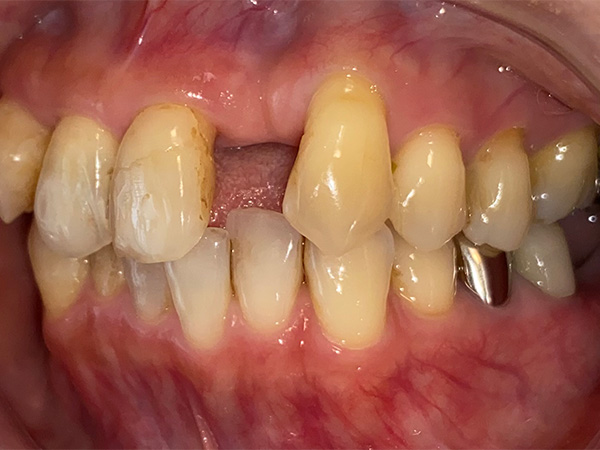

インプラント症例その1

術前

① 年齢層(一般的傾向) 60代

② 性別 女性